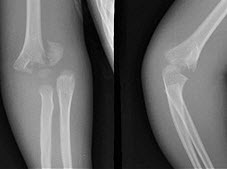

E.以上都不是

160、单项选择题

8岁,男孩,外伤后感左肘关节肿痛,左肘关节正侧位摄片如图,下列哪项描述错误()

A.“八”字征

B.“X”线白线不连续

C.软组织肿胀

D.左肱骨小头骺线增宽

E.以上均正确